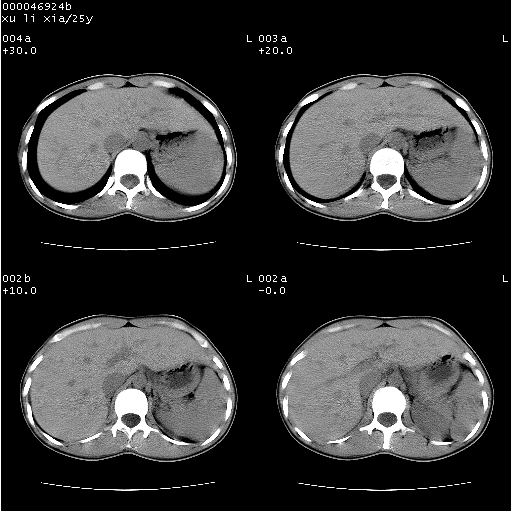

患者 女,25岁。因“左侧卵巢肿瘤”术前胸片偶然发现两肺病变。平素无明显不适,无呼吸系统症状及体征,无传染病史。

盆腔ct扫描(ps+ce)提示:左侧附件区畸胎瘤。

临床诊断:1)左侧卵巢肿瘤。2)两肺感染性病变。